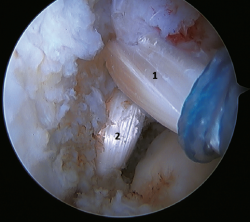

Un reciente consenso(64) recomienda la reconstrucción del LTFA y el LCF (Figuras 5 y 6) en aquellos casos de laxitud generalizada o cuando existe una mala calidad tisular. Otras indicaciones serían cuando existen dudas de la estabilidad subtalar o en aquellos pacientes con rotura del LCF. Para algunos autores, el IMC superior a 30 kg/m2 también sería una indicación para esta técnica.

Figura 6. Imagen artroscópica de una doble reconstrucción con aloinjerto del ligamento talofibular anterior (1) y del ligamento calcaneofibular (2), objetivándose la correcta tensión y posicionamiento de los fascículos.